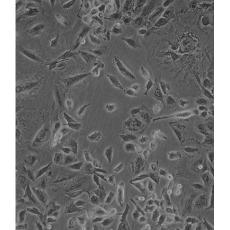

NCI-H1975

中文名稱 人肺腺癌細胞

組織來源 肺腺癌;女性

細胞種屬 Homo sapiens, human

生長特性 adherent

形態特征 epithelial

細胞描述 該細胞是1988年7月從一名女性(無抽煙史)非小細胞肺腺癌組織中分離得到的。